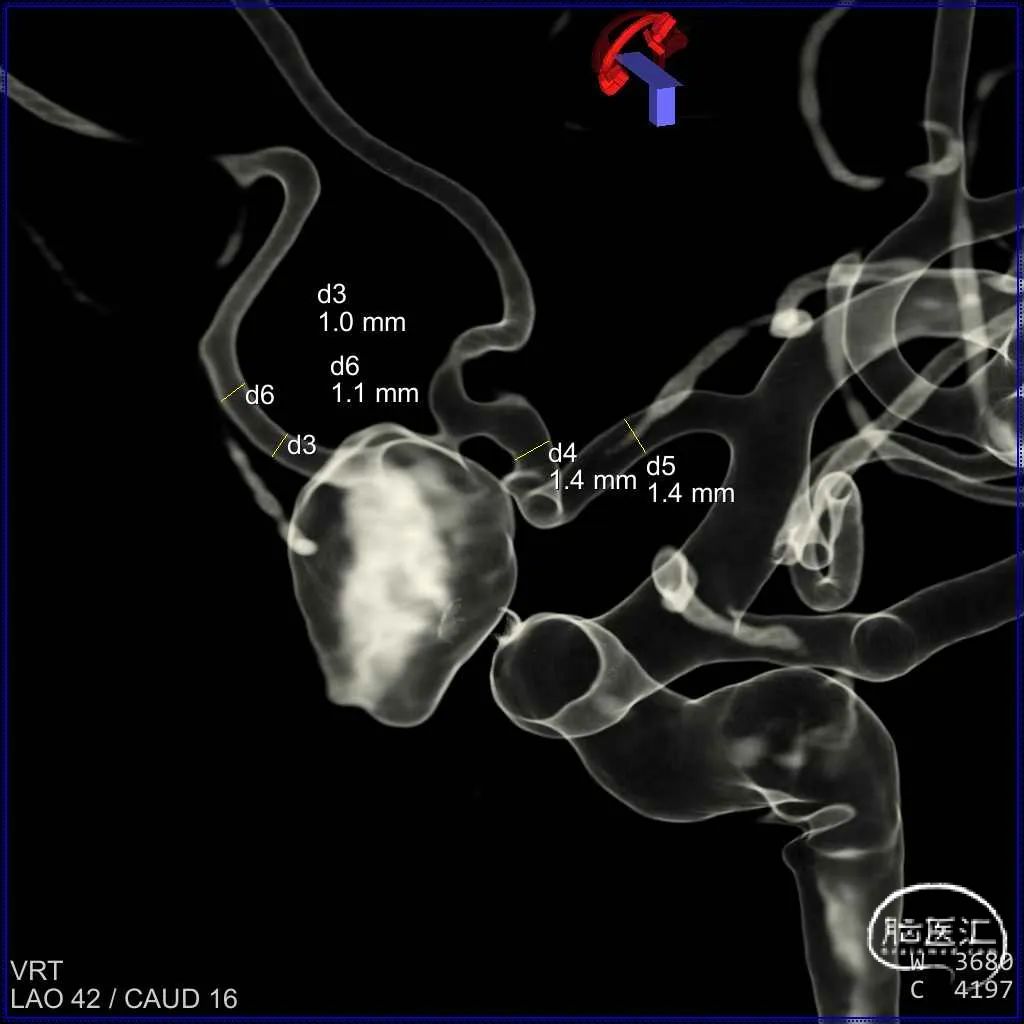

三维造影重建

载瘤血管管径测量

三维重建测量瘤体、瘤颈及预估支架长度:

初步诊断:大脑前动脉动脉瘤。

位置:左侧大脑前动脉动脉瘤。

动脉瘤的形态:宽颈囊状,瘤内附壁血栓,造影可显影动脉瘤体积约为原始动脉瘤1/3。

动脉瘤大小(mm):长 10.8;宽 7.4;高 6.8

动脉瘤颈宽度(mm):3.7

载瘤动脉直径(mm):远端 1.1;近端 1.4

左侧大脑前动脉发育不全,远端仅有两支分支血管供应额极部位,动脉瘤由其中一分支发出,余左侧大脑前动脉供血区由对侧大脑前动脉供血。大型动脉瘤考虑为夹层性质,瘤内大量附壁血栓形成,造影可显示动脉瘤体积约为原始动脉瘤的1/3。